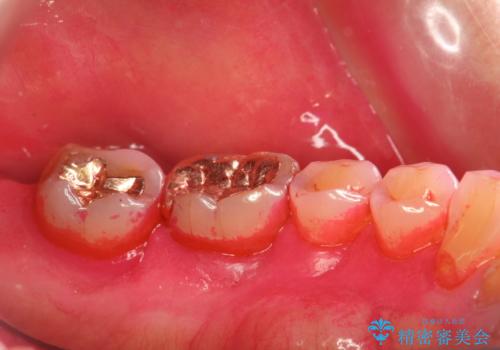

- 定期的にメンテナンスにいらしている方です。日々の歯磨きチェックとクリーニング希望でした。PMTC30分コースと、歯磨き指導を行いました。

歯垢染色液を使うと、一見きれいな歯でも染まっている所が全て歯垢(プラーク)なのがはっきり分かります。歯に付着した歯垢(プラーク)は肉眼では認識しにくいものです。完璧に磨けているつもりでも、磨き残しが残っているかもしれません。

毎日の歯磨きだけでは、隅々までキレイに磨くことは困難です。さらに、体調不良や疲労などで免疫が低下しているとお口の中の細菌が増えやくなることがあります。